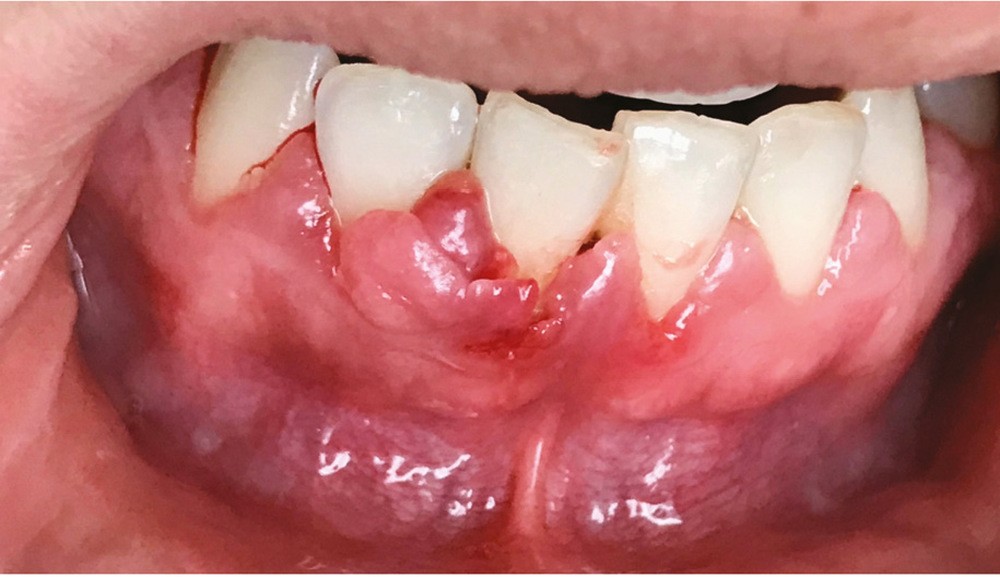

Les modifications hormonales à mettre en relation avec l’hygiène bucco-dentaire, les paramètres socio-économiques, l’âge précoce de la grossesse ainsi que l’augmentation du grignotage pourraient augmenter la prévalence des caries dentaires chez la femme enceinte. Ces patientes sont régulièrement sujettes à des envies multipliant le nombre de prises alimentaires souvent très riches en sucre. Ces apports sucrés, associés à la baisse du pH salivaire lors de la grossesse, entraînent un déséquilibre du cycle déminéralisation et de reminéralisation. Le risque carieux peut être augmenté, ainsi que la susceptibilité à l’érosion dentaire accrue par les vomissements et/ou les reflux gastro-œsophagiens [2]. L’action hormonale peut également avoir des répercussions sur les tissus parodontaux. La gingivite gravidique observée sur plus d’une femme enceinte sur deux, constitue une réponse inflammatoire de la gencive exacerbée par la présence de plaque bactérienne, et favorisée par l’augmentation des taux d’œstrogène et de progestérone [3] (fig. 1). 5 % des futures mères développeront un épulis, dont l’étiologie reste méconnue (fig. 2) [4].